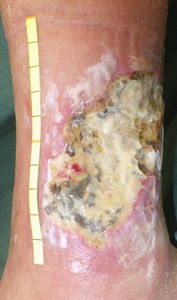

85歳女。

2018年11月12日,左下腿蜂窩織炎で〇〇病院皮膚科を受診し入院し,抗生剤点滴を受けたが,下腿に水疱ができて傷になったためゲーベンクリーム®で治療。11月30日に退院となり,ゲーベンクリーム®が処方されたが,傷はさらに拡大した。外来では,感染して傷が深くなったので,細菌を除去するためにボディーソープでゴシゴシ洗うように指導された。キズはさらに広がった。12月25日,転倒して右足を捻挫し,△△病院整形外科に入院となったが,創部はゲーベンクリームの治療を継続。主治医から「この傷は治らないので,足切断が必要」と説明された。

2019年1月8日,当院受診。ズイコウパッドで治療。

| 1月8日 | 2月4日 27日後 |